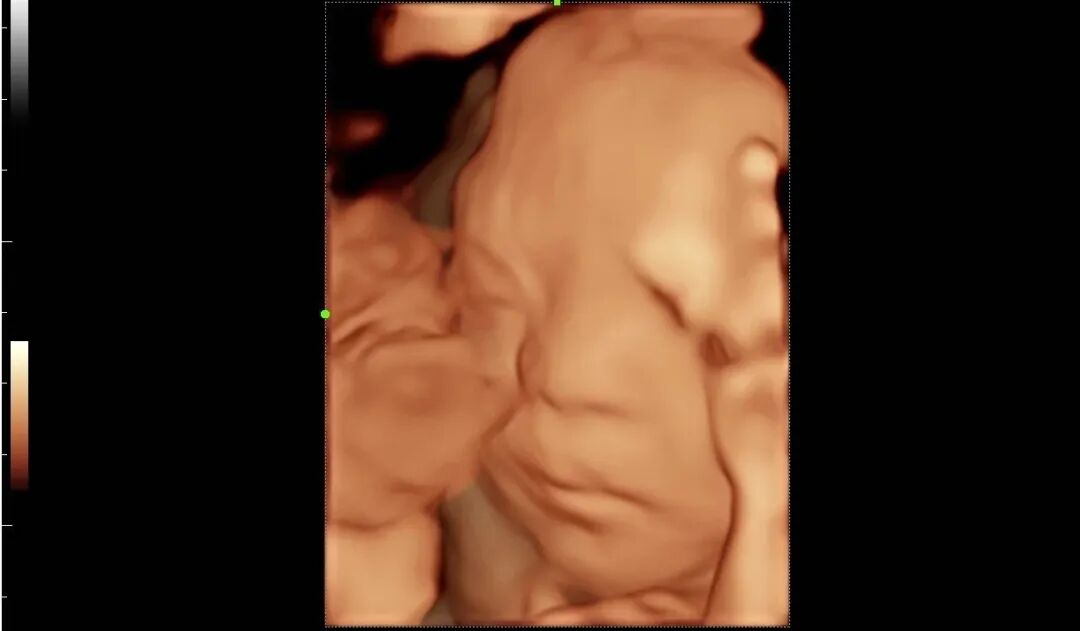

为进一步提高我院诊疗检查与诊断水平,不断满足城乡患者日益增长的就医需求,健全和完善医疗保障体系。2022年12月我院引进了mindray- Resonal9T高端彩色多普勒超声系统正式投入使用,此设备具备超声介入、超声造影、超声高帧率 STE 剪切波弹性成像及应变式弹性成像(甲状腺、乳腺、肝脏),二维、三维、四维、阴式、盆底、心脏及血管超声等功能。此设备的引进标志着海伦影像学科将跨越新的高度,以此助力城乡百姓解决看病难,看病贵的就医难题!